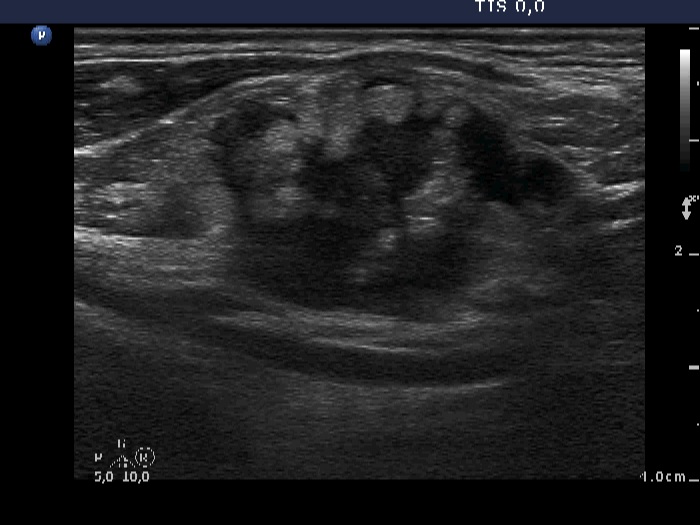

Ultrasonography: The thyroid was intact. There were multiple nodes in both supraclavicular regions. The nodes presented an absolutely irregular shape and border. They contained numerous hyperechogenic circumscribed areas.